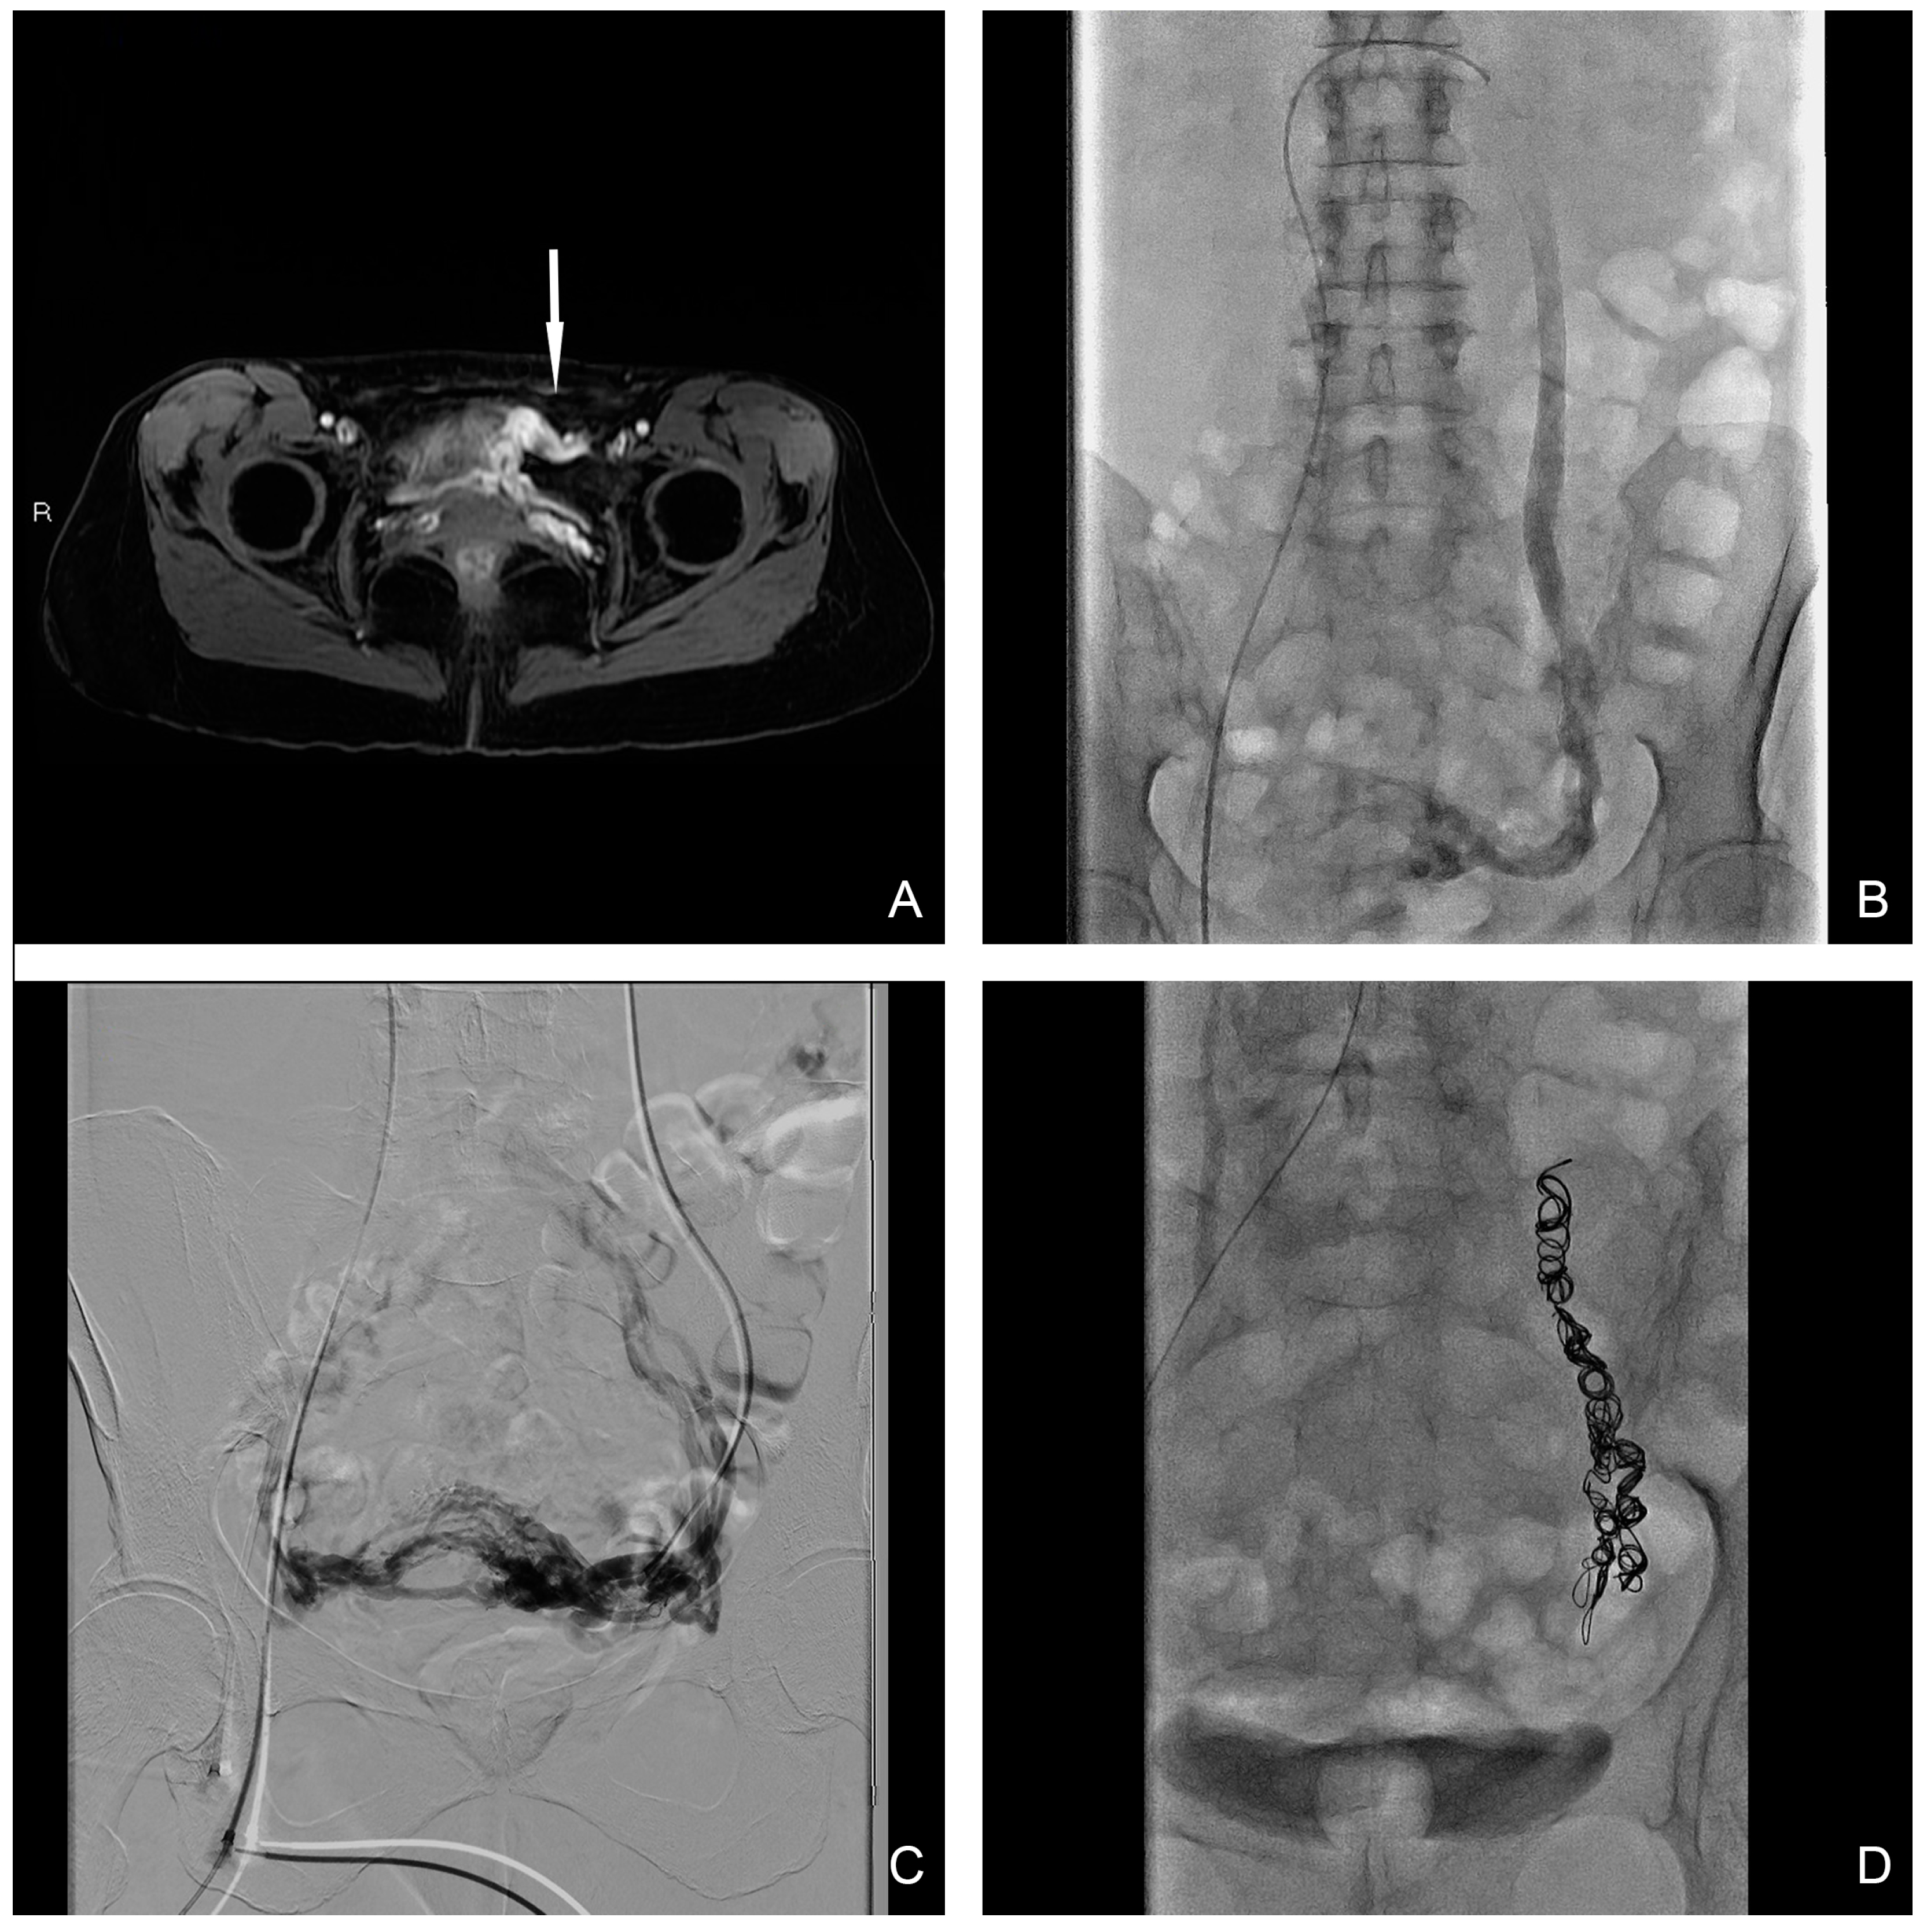

Endovascular technique. The procedure was undertaken in inpatient conditions with mild analgosedation. Bilateral ovarian and iliac diagnostic subtraction phlebography was performed from femoral access to delineate the anatomy and identify the main vessels and collateral pathway, obtained with and without provocation such as the Valsalva maneuver. Ovarian catheterization was achieved with a 5 Fr HET or another shaped-tip catheter (COOK Medical, Bloomington, IN, USA) with a 0.038″ lumen depending on the type of coil utilized. In the case where the 0.018″ micro-coils platform was utilized, a 2.7 Fr Progreat Terumo (Terumo Medical, Tokyo, Japan) was used for delivery. A sandwich technique was preferred in all cases with pushable coils used after the distal injection of 3% sodium tetradecyl sulphate (STS), prepared as a foam according to the Tessari method, with a maximum dose per procedure of 10 mL [15]. Complete occlusion with the entire length of the incompetent vein prevented possible future recanalization. Coils’ common sizes range from 8 mm to 20 mm, and are generally oversized to prevent migration. Internal iliac veins were embolized with the same sandwich technique in cases where a venous reflux was confirmed at phlebography during the Valsalva maneuver. Final phlebography control after embolization was undertaken to confirm vessel occlusion. In patients with symptomatic uterine myomas, a bilateral uterine artery embolization (UAE) was performed in the same session. All procedures were performed by an interventional radiology radiologist with more than 5 years of experience. The primary cause of PCS was left ovarian vein reflux, highlighted in all 32 patients (100%) (Figure 2), while in 8 cases the insufficiency was bilateral; moreover, in 2 cases internal iliac vein insufficiency was demonstrated. Ovarian vein embolization was performed in all 32 patients (100%) after demonstrating reflux during the phlebographic study (just on the left side in 24 patients (75%) and bilaterally in 8 patients (25%)). The internal iliac veins were embolized only in 2 cases (6.25%), 1 on the right side and 1 on the left side, where the reflux was demonstrated from leakage points after bilateral ovarian embolization. Findings from pelvic phlebography with fluoroscopy and therapeutic details are summarized in Table 3.

Figure 2.

(A) T1 water–lava axial MRI scan shows peri-uterine plexus bilaterally dilatated with tortuous course and a maximum caliber of 6 mm (white-arrow). (B,C) Selective and superselective diagnostic phlebography through a 5 Fr catheter demonstrates ovarian vein dilation with reflux in the para-uterine veins and partial drainage in internal iliac veins. (D) Final image after sclero-embolization procedure.